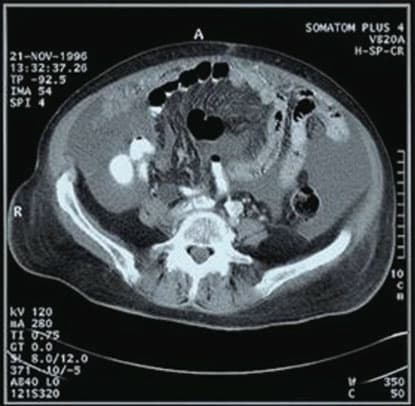

A first version of these materials is light-insensitive and requires heating only in the specific spots where a black image is required. This is achieved by the use of digitally controlled thermal heads in contact with the material. This thermographic writing is commercialized for the production of medical hard-copies, e.g. digital X-ray images can be written to a hard copy in this way. Other applications such as inkless printing of labels or tags or any other image are feasible.